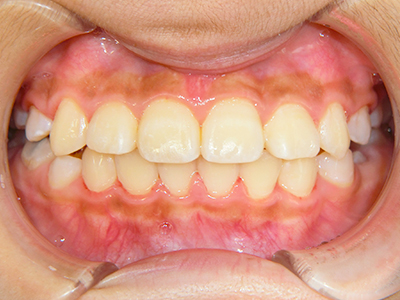

【4】矯正治療

矯正装置を装着し、調整しながら少しずつ歯を移動させ、歯並びを整えていきます。

状態によって家庭でのトレーニングが必要な場合もあり、治療期間も個人差があります。